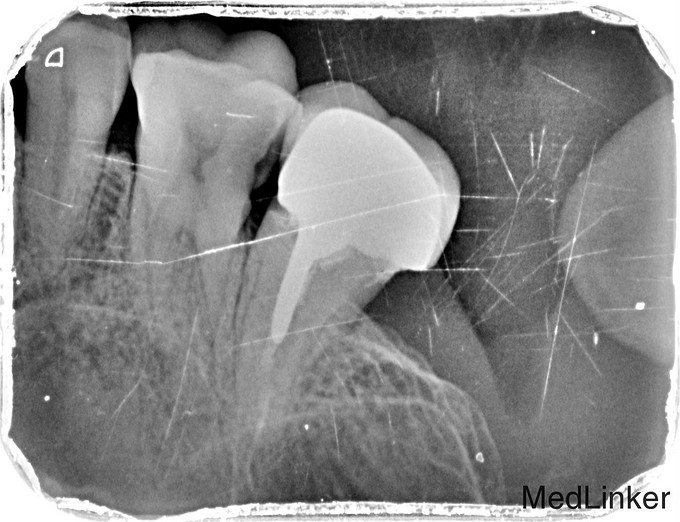

主诉:右上后牙食物嵌塞不适数日 现病史:数日来,患者右上后牙食物嵌塞疼痛不适影响进食来诊。 既往史:健康 过敏史:无

临床检查:16牙合面无明显的龋坏,远中邻面探(++),冷(++),叩(-),松动度(-),牙周红肿.牙石一度。 辅助检查:X线示16根尖周牙周膜增宽。远中邻面部分吸收。

诊断:16慢性牙髓炎 治疗:16局麻降牙合,开髓拔髓寻找根管口,建立直线通路,扩通根管,确定工作长度。S3/EDTA凝胶镍钛器械,低浓度次氯酸钠冲洗根管,预备至25/06,氢氧化钙诊间封药,牙周洁治,抗炎治疗 ,一周后复诊,试主尖X线示恰充,试干根管,导AH-PLUS糊剂,VDW热压胶垂直加压根充,术后见根管恰充,暂封观察择期桩冠修复。